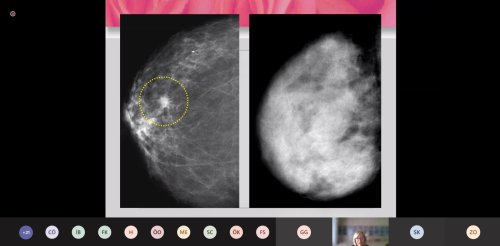

Meme kanseri tarama cihazı mamografi hakkında bilgi veren Prof. Dr. Oktay, “Etkinliği kanıtlanmış bir yöntem olan ve taramada kullanılan görüntüleme yöntemi mamografidir. Bu tarama yöntemi, çok az düzeyde x ışını kullanarak, memenin görüntüsünü elde etmektir. Özellikle günümüz teknolojilerinde dijital mamografide memeye verilen radyasyon dozu oldukça düşüktür. Bu doz günlük hayatta aldığımız zemin radyasyonuna oldukça yakındır. Bir mamografi dozu iki aylık zemin radyasyonuna neredeyse eş değerdir. Bu nedenle, mamografi cihazından çıkan radyasyonun kanser oluşumunda bir etken değildir. Momografi henüz ele gelmeyen, klinik olarak saptanma aşamasına gelmeyen lezyonu preklinik evre dediğimiz evrede ortaya koyabiliyor. Taramada amacımız; erken tanıyı ortaya çıkarmak ve doğal seyrini değiştirebilmektir. Amacımız, ölümleri azaltmaktır. Geniş olguyu içeren Uluslararası Kanser Ajansı'nın derlediği bir sonuca göre tarama ortamına davet edilen kadınlarda yüzde 23’ü, taramaya bizzat katılan kadınlar içinde de mamografi kullanıldığı takdirde yüzde 40 gibi ölüm riskinin azaldığı göstermiş" diye konuştu.

Mamografi kullanımını özellikle 40 yaşın üzerindeki kadınlara öneren Prof. Dr. Oktay, "Kadınlarda 40 yaşından sonra, 1-2 yıllık periyotlarda mamografi çekimi yaptırmayı öneriyoruz. Yıllık klinik muayene de oldukça önemlidir. Kadın doğum kontrollerinde, aile hekimleri, cerrahi kliniklerinde de yapılabilir. 40 yaşının altında ise 3 yılda bir doktor muayenesi yapılması ideal bir öneridir. Bunların yanı sıra kadınının aylık kendi memesine yaptığı muayane de oldukça önem taşır. Mamografi tek başına mükemmel bir yöntem değil. Farklı nedenlerden dolayı bazı kanserler saptanamayabilir. Yağlı meme içerisinde kitle sıkışınca cihaz kitleyi algılayamıyor ama ultrasonda bir kitle olduğu saptanabilmektedir. Bu nedenle, ek tetkik olarak ultrasonu öneriyoruz. Radyolojik taramalar, bunun yanı sıra kadının farkındalığı meme kanserinin ortaya çıkarılmasında anahtar role sahiptir." diye konuştu.